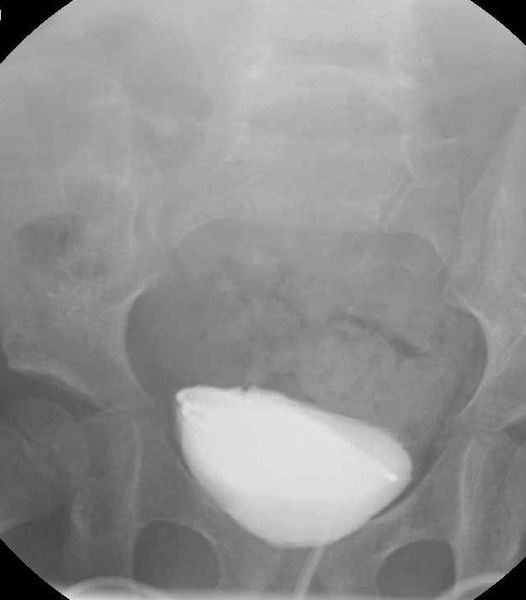

Cystografie